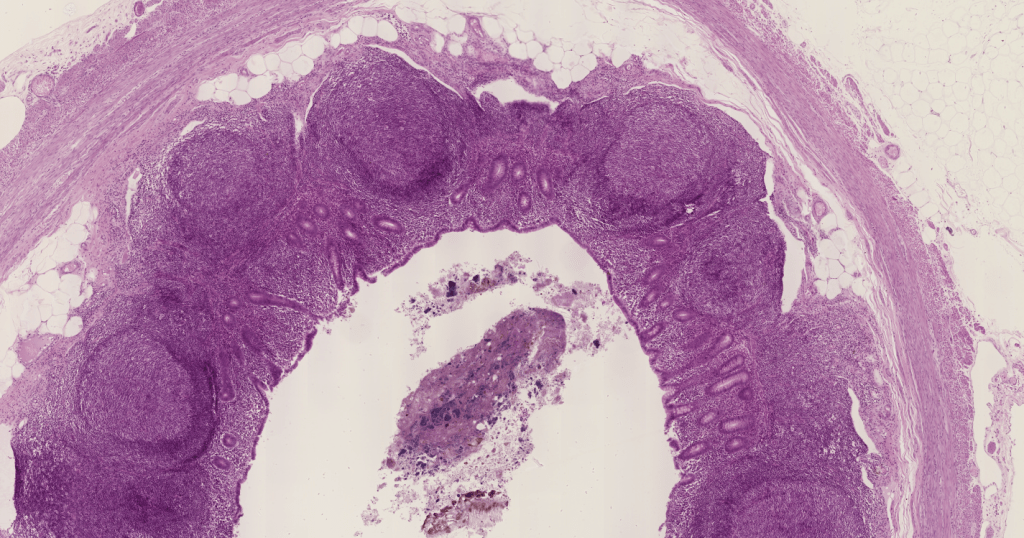

Los ganglios linfáticos son órganos linfoides arriñonados de 2-20mm de diámetro. La linfa se filtra a través de ellos.Los ganglios son órganos linfoides encapsulados con presencia de nódulos linfáticos en su corteza.Algunas de sus funciones principales son la filtración de linfa antes de devolverla al conducto torácico, la producción de linfocitos que se añaden a la linfa y la recirculación de linfocitos.Observe la cápsula de TCDi y los nódulos linfoides en la corteza.Con impregnaciones argénticas podemos observar fibras reticulares (Colágena III)Identifique.